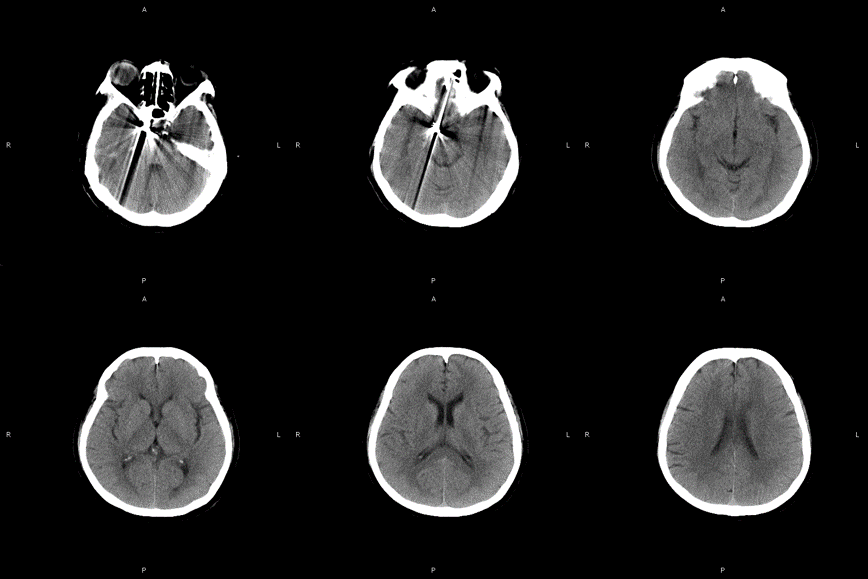

10. 术后复查造影可以看到,动脉瘤实现Raymond I级栓塞,CT复查也没有异常。希望这个病人能有个好的预后,也期待这个病例的随访结果。

Final

术后CT